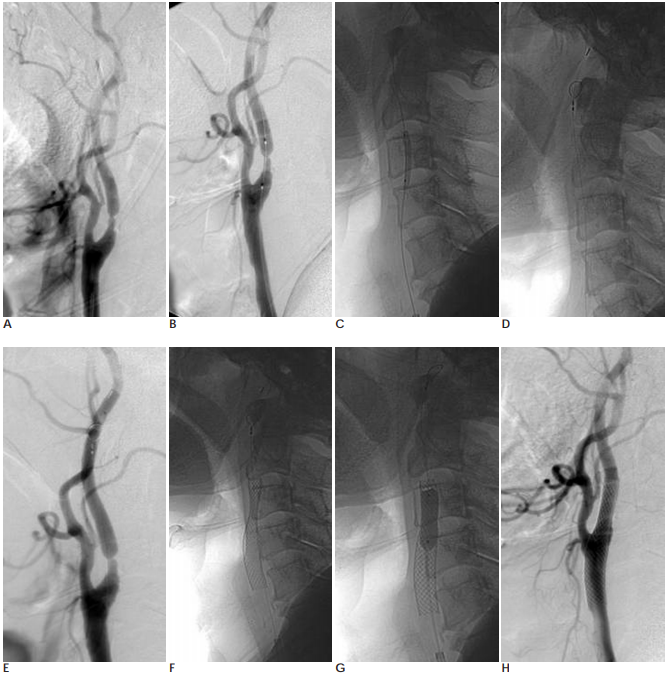

경동맥 스텐트설치술은 대퇴동맥에 관을 삽입하여 경동맥 협착증이 있는 부위에 스텐트라는 금속 그물망을 펼쳐 좁아진 혈관을 넓혀주는 방법입니다. 전신 마취하여 목 부분과 경동맥을 직접 절개한 후 동맥경화성 물질이 침착되어 있는 혈관내막을 제거하는 경동맥 내막절제술은 오래전부터 시행되어왔던 치료 방법입니다. 하지만 전신마취의 필요 없이 대퇴동맥으로 작은 관을 삽입하여 경동맥 협착이 있는 부위에 풍선과 스텐트라는 금속 그물망을 펼쳐 좁아진 혈관을 넓혀주는 경동맥 스텐트 설치술이 수술보다 덜 침습적이면서 흉터도 없고 회복도 빠르다는 장점 때문에 최근에는 경동맥 스텐트 설치술 선호되고 있고 있습니다.